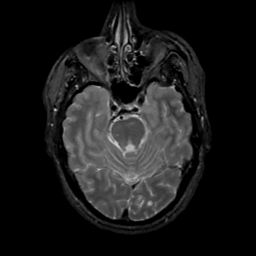

MR Study #4, March 3, 1991 -- Slice #16

[Home][Help][Clinical][Tour 1][Tour 2] Slice 16